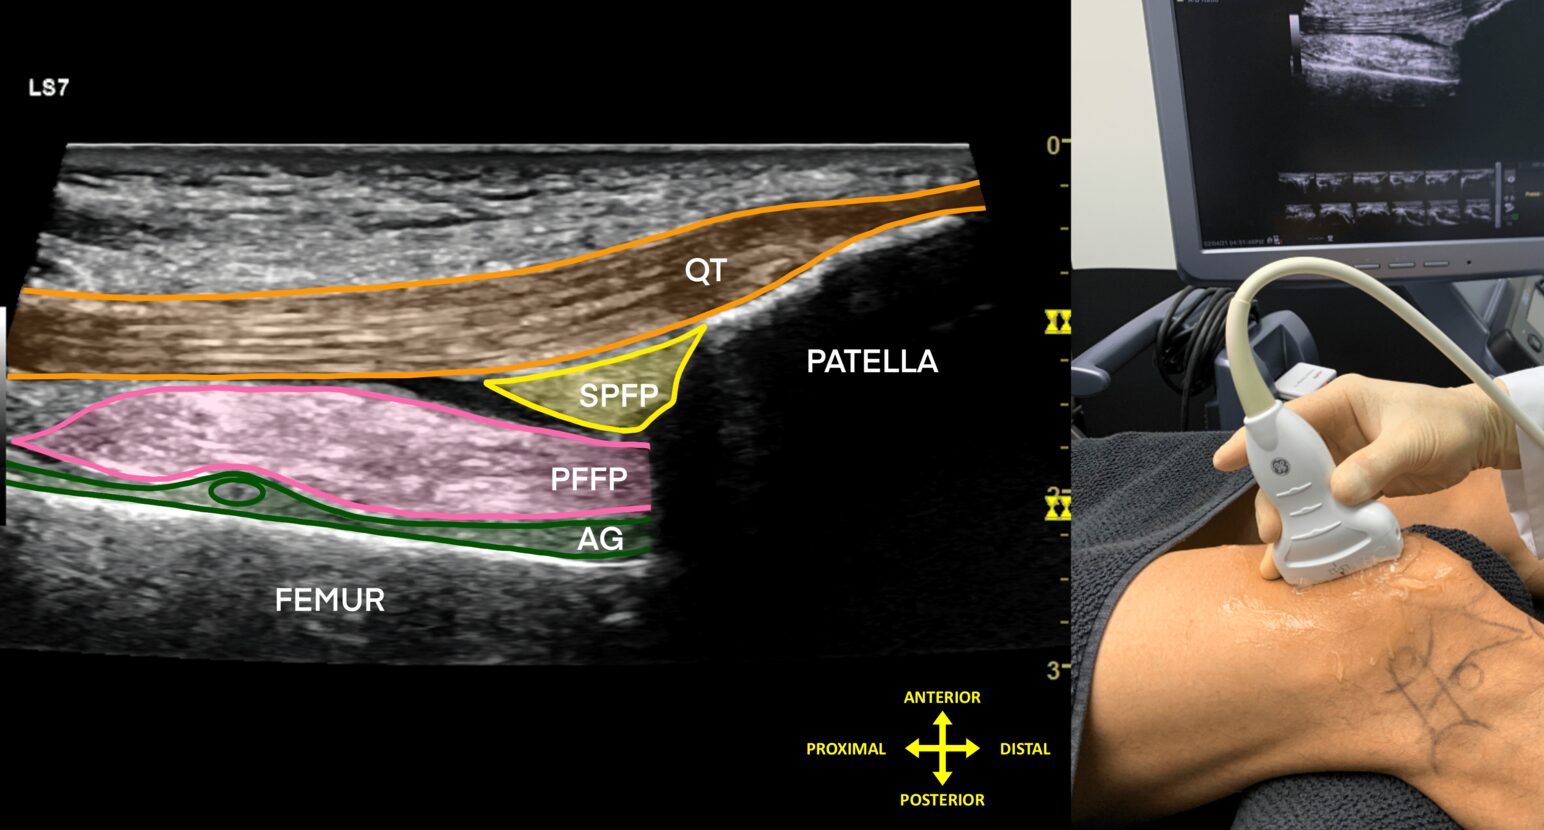

Sonoanatomy of the anterior, lateral, medial, and posterior knee, varus and valgus tests, and flexion and extension tests in different patient positions.

Provides guided protocols for diagnostic ultrasound assessment in the knee region.

Includes scans and explanations of common knee pathologies, along with dynamic assessments.

High-resolution ultrasound images, detailed anatomical illustrations, functional anatomy visuals, dynamic tests, and animations.